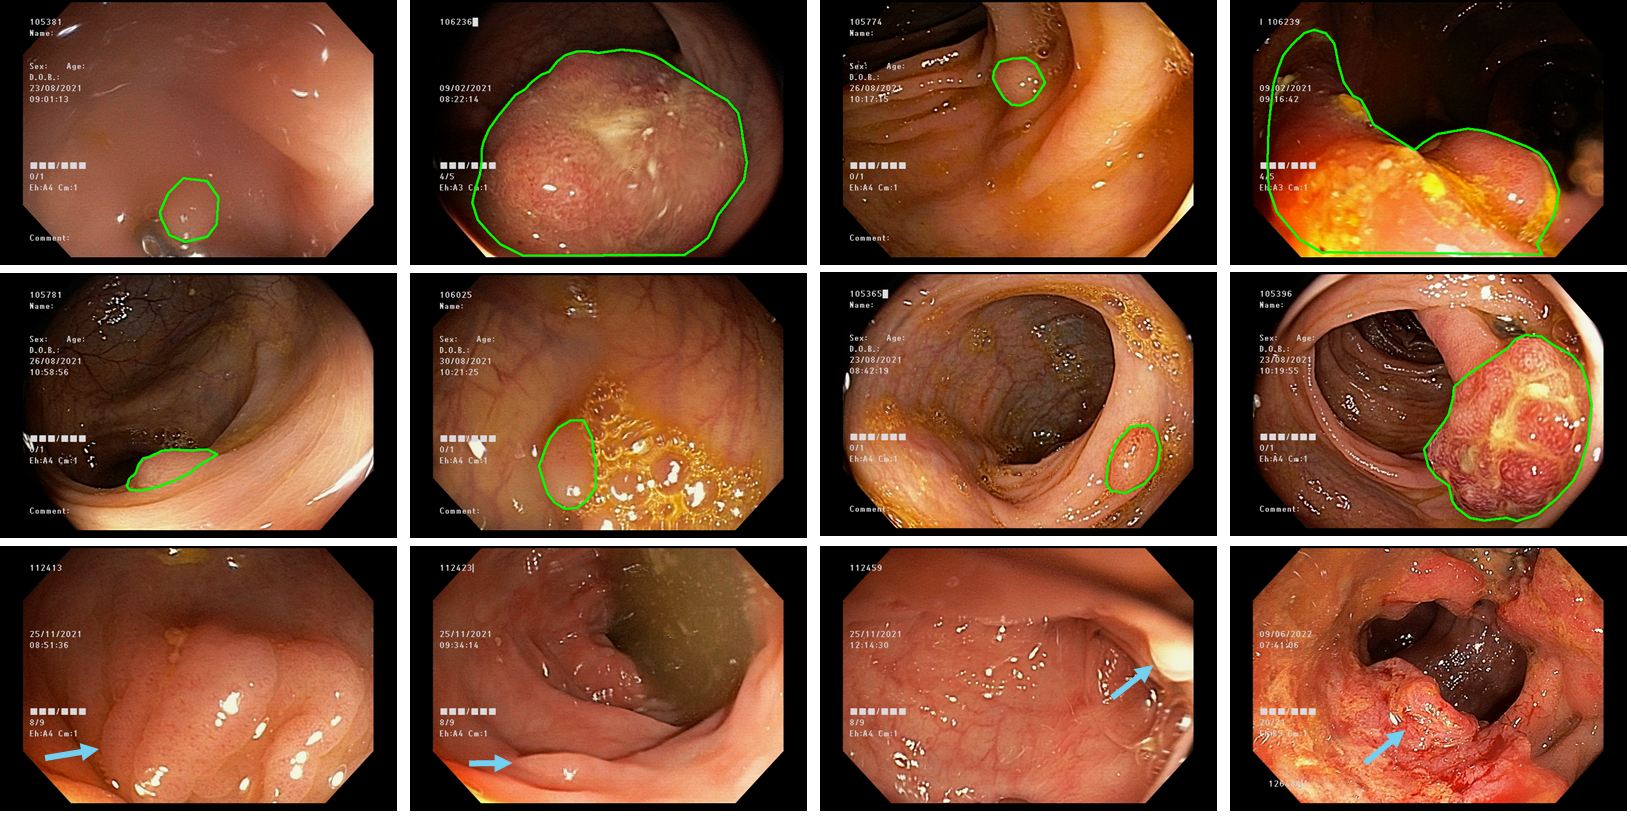

Figure 3 shows visual representations of various polyps. highlighting their morphological, size, and texture variability. Additionally, it showcases the impact of water bubbles and intestinal residues in the extracted samples, adding complexity to the detection task. The green contours in the images represent the boundaries of polyps taken from the expert annotation. In the last row, the blue arrows draw attention to some structures that exhibit patterns resembling polyps, such as specular reflections or mucous. These observations complement the dataset analysis mentioned earlier, emphasizing the challenges associated with accurate polyp recognition.